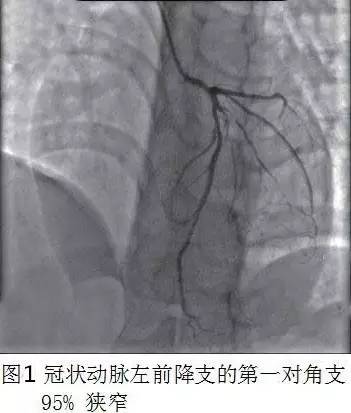

诊疗经过:本例患者血TC和LDL-C异常增高,外周动脉(颈动脉)明显的粥样硬化斑块,行冠状动脉造影提示左前降支的第一对角支处95%狭窄(图1)、回旋支中段见粥样斑块。诊断:冠状动脉粥样硬化性心脏病。给予依那普利、美托洛尔、拜阿司匹林、并将氟伐他汀40 mg Qd改为阿托伐他汀40 mg Qd进行正规二级预防,嘱坚持服用并定期复查。